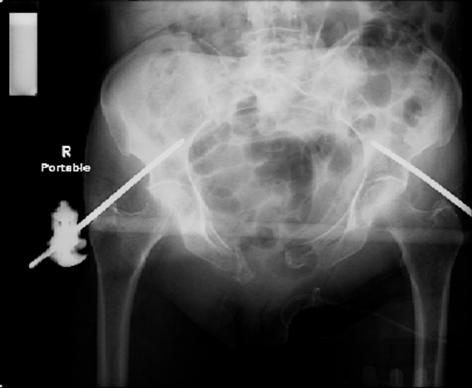

so the question is what next operatively if anything? concerns are infection, nonunion anteriorly and possible incompetence of the pelvic floor which may lead to prolapse issues. right rami are comminuted and plating may entail ilioinguinal approach to extend plate laterally to right iliac wing. retrograde screw up right rami is an option but I am not convinced it will add much. adding SI screws very doable, but major concern is restoring anterior ring. so far wound is clean and closed over a drain, and I have no plans to open it back up and wash again.

maintaining pelvic alignment in ex-fix in 70 yo female for any length of time may be challenging.

any thoughts? would anyone plate the pubic symphysis to close the gap and leave the more lateral rami fractures alone? the most recent pelvic case on this website involved pts with suprapubic catheters and antibiotic options including resorbable beads. I wonder how many people would plate and place antibiotic beads. thanks.